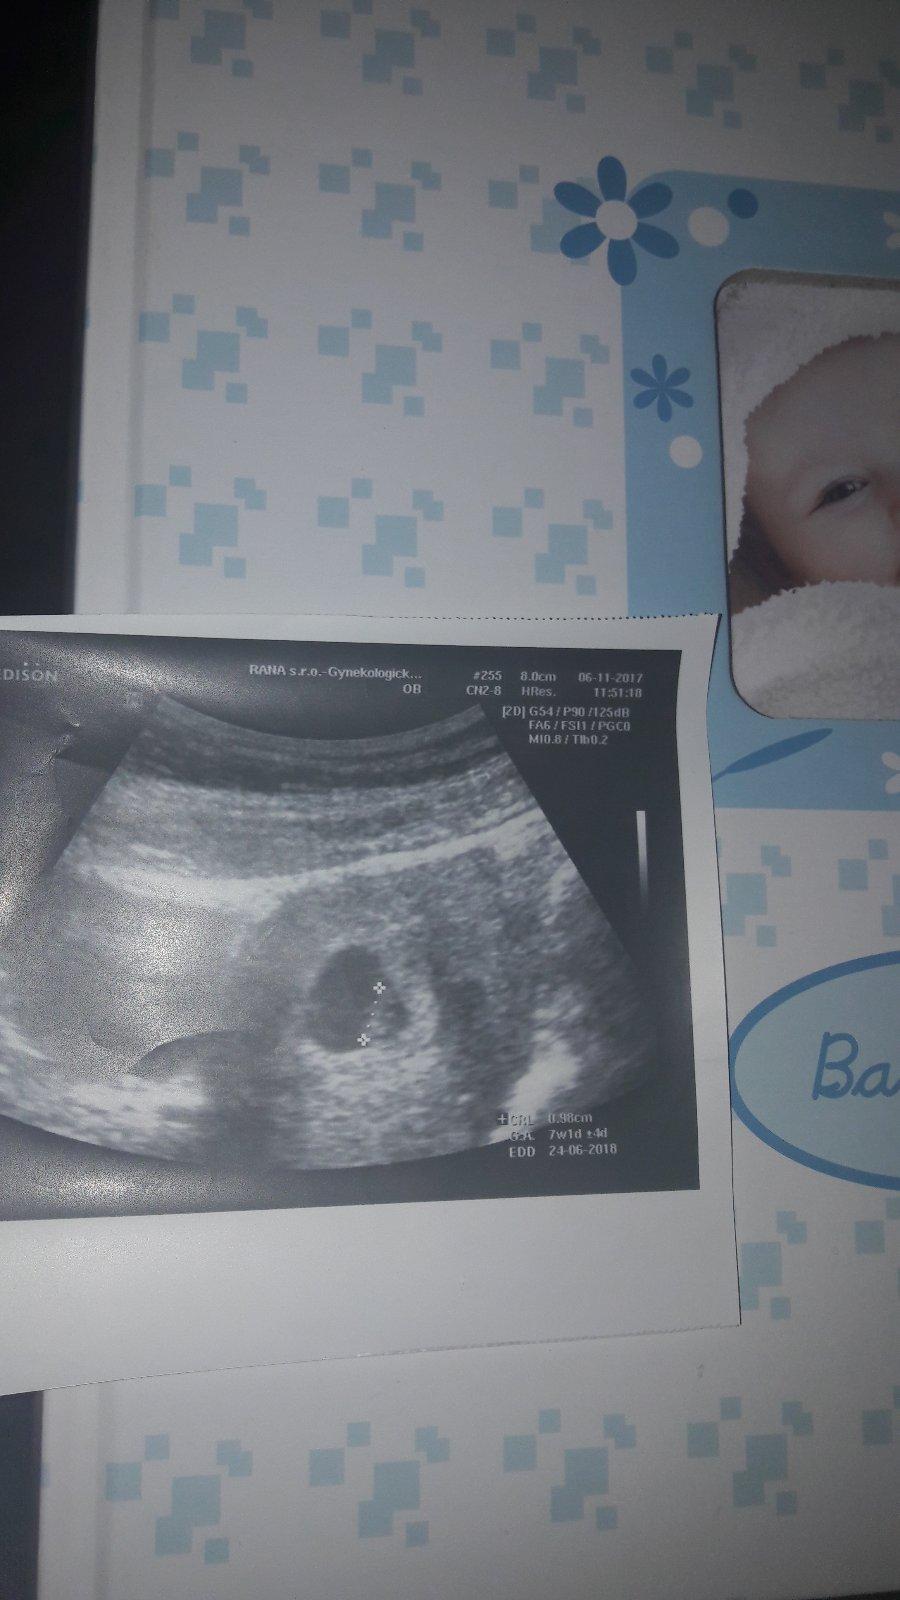

@nellynnnka nie...práveže ta machulka bola len ten plodovy vak ...o 10 dni cca už bolo aj babo ..to som.bola 7tt+1 ...